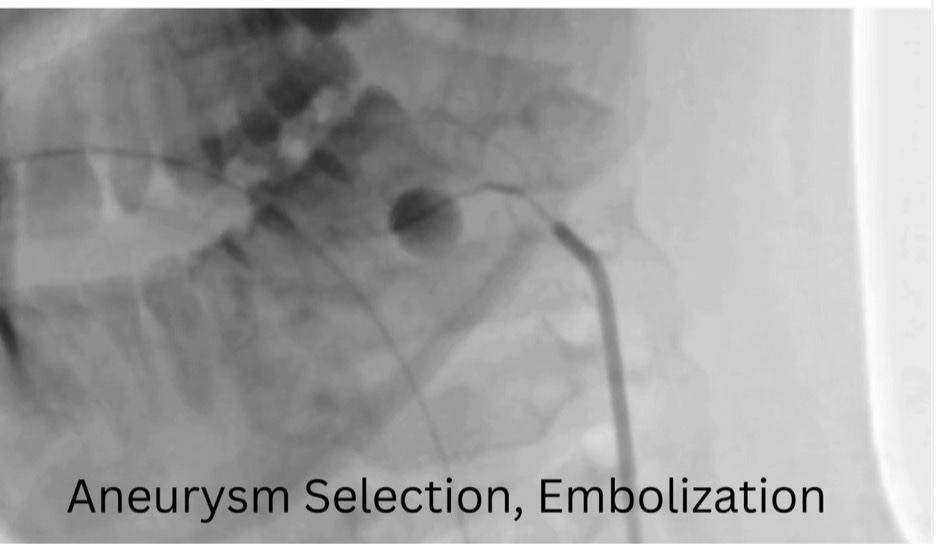

ومن جانبه، ذكر الدكتور احمد كمال، المدير التنفيذي للمستشفيات الجامعية، أنه تم تجهيز وحدة القسطرة على الفور، حيث نجح الفريق الطبي في غلق التمدد الشرياني باستخدام حلزونات دقيقة عبر القسطرة التداخلية، مما أسهم في السيطرة الكاملة على النزيف دون الحاجة إلى جراحة تقليدية، وتقليل احتمالات المضاعفات.